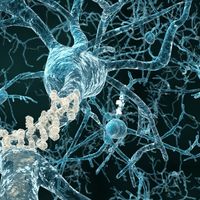

Deficient DNA Repair Mechanism May Contribute To Alzheimer’s

Deficient DNA Repair Mechanism May Contribute To Alzheimer’s